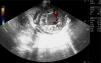

La miocardiopatía no compactada es una entidad poco frecuente asociada a complicaciones como insuficiencia cardiaca, fenómenos cardioembólicos, arritmias y muerte súbita. De etiología del todo no aclarada, presenta una base genética. Su diagnóstico está aumentando debido al uso de la ecocardiografía, y se caracteriza por el engrosamiento de la pared del ventrículo izquierdo con prominencias y recesos con ausencia de compactación del miocardio, diferenciándose dos capas: miocardio compactado y no compactado (fig. 1). Es característico visualizar en Doppler color de flujo sanguíneo entre dichas criptas sin comunicación con el sistema coronario (figs. 2 y 3), pudiendo originar embolias.